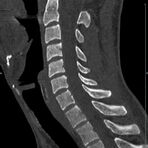

Wirbelsäule

• Darstellung von Frakturen, Tumoren und Bandscheibenveränderungen